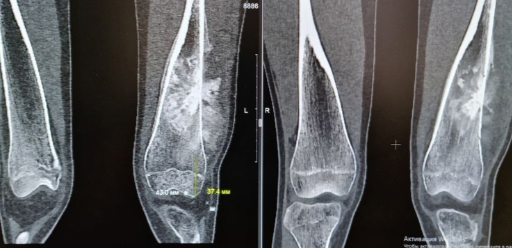

Страшный диагноз 15-летней нижегородке поставили после того, как у девушки начались сильные боли в коленном суставе. Опухоль обнаружили вовремя – она не успела дать метастазы, и врачи приняли решение о безотлагательном хирургическом лечении.

Операции по эндопротезированию коленного сустава очень редки, в целом по стране ежегодно их проводят 60-70, главным образом – в федеральных онкологических центрах. Но теперь такая помощь станет доступна и в Нижегородской области.